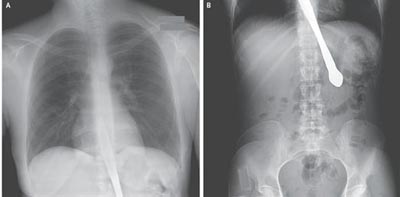

На скорой неудавшуюся трюкачку доставили в медицинский центр для обследования. Медики, сделав рентген, установили, что пищевод и желудок пациентки остались неповрежденными, хирургическое вмешательство не потребовалось.

Для того чтобы достать нож, специалисты провели процедуру гастроскопии, после чего освободили даму от проглоченного "реквизита".